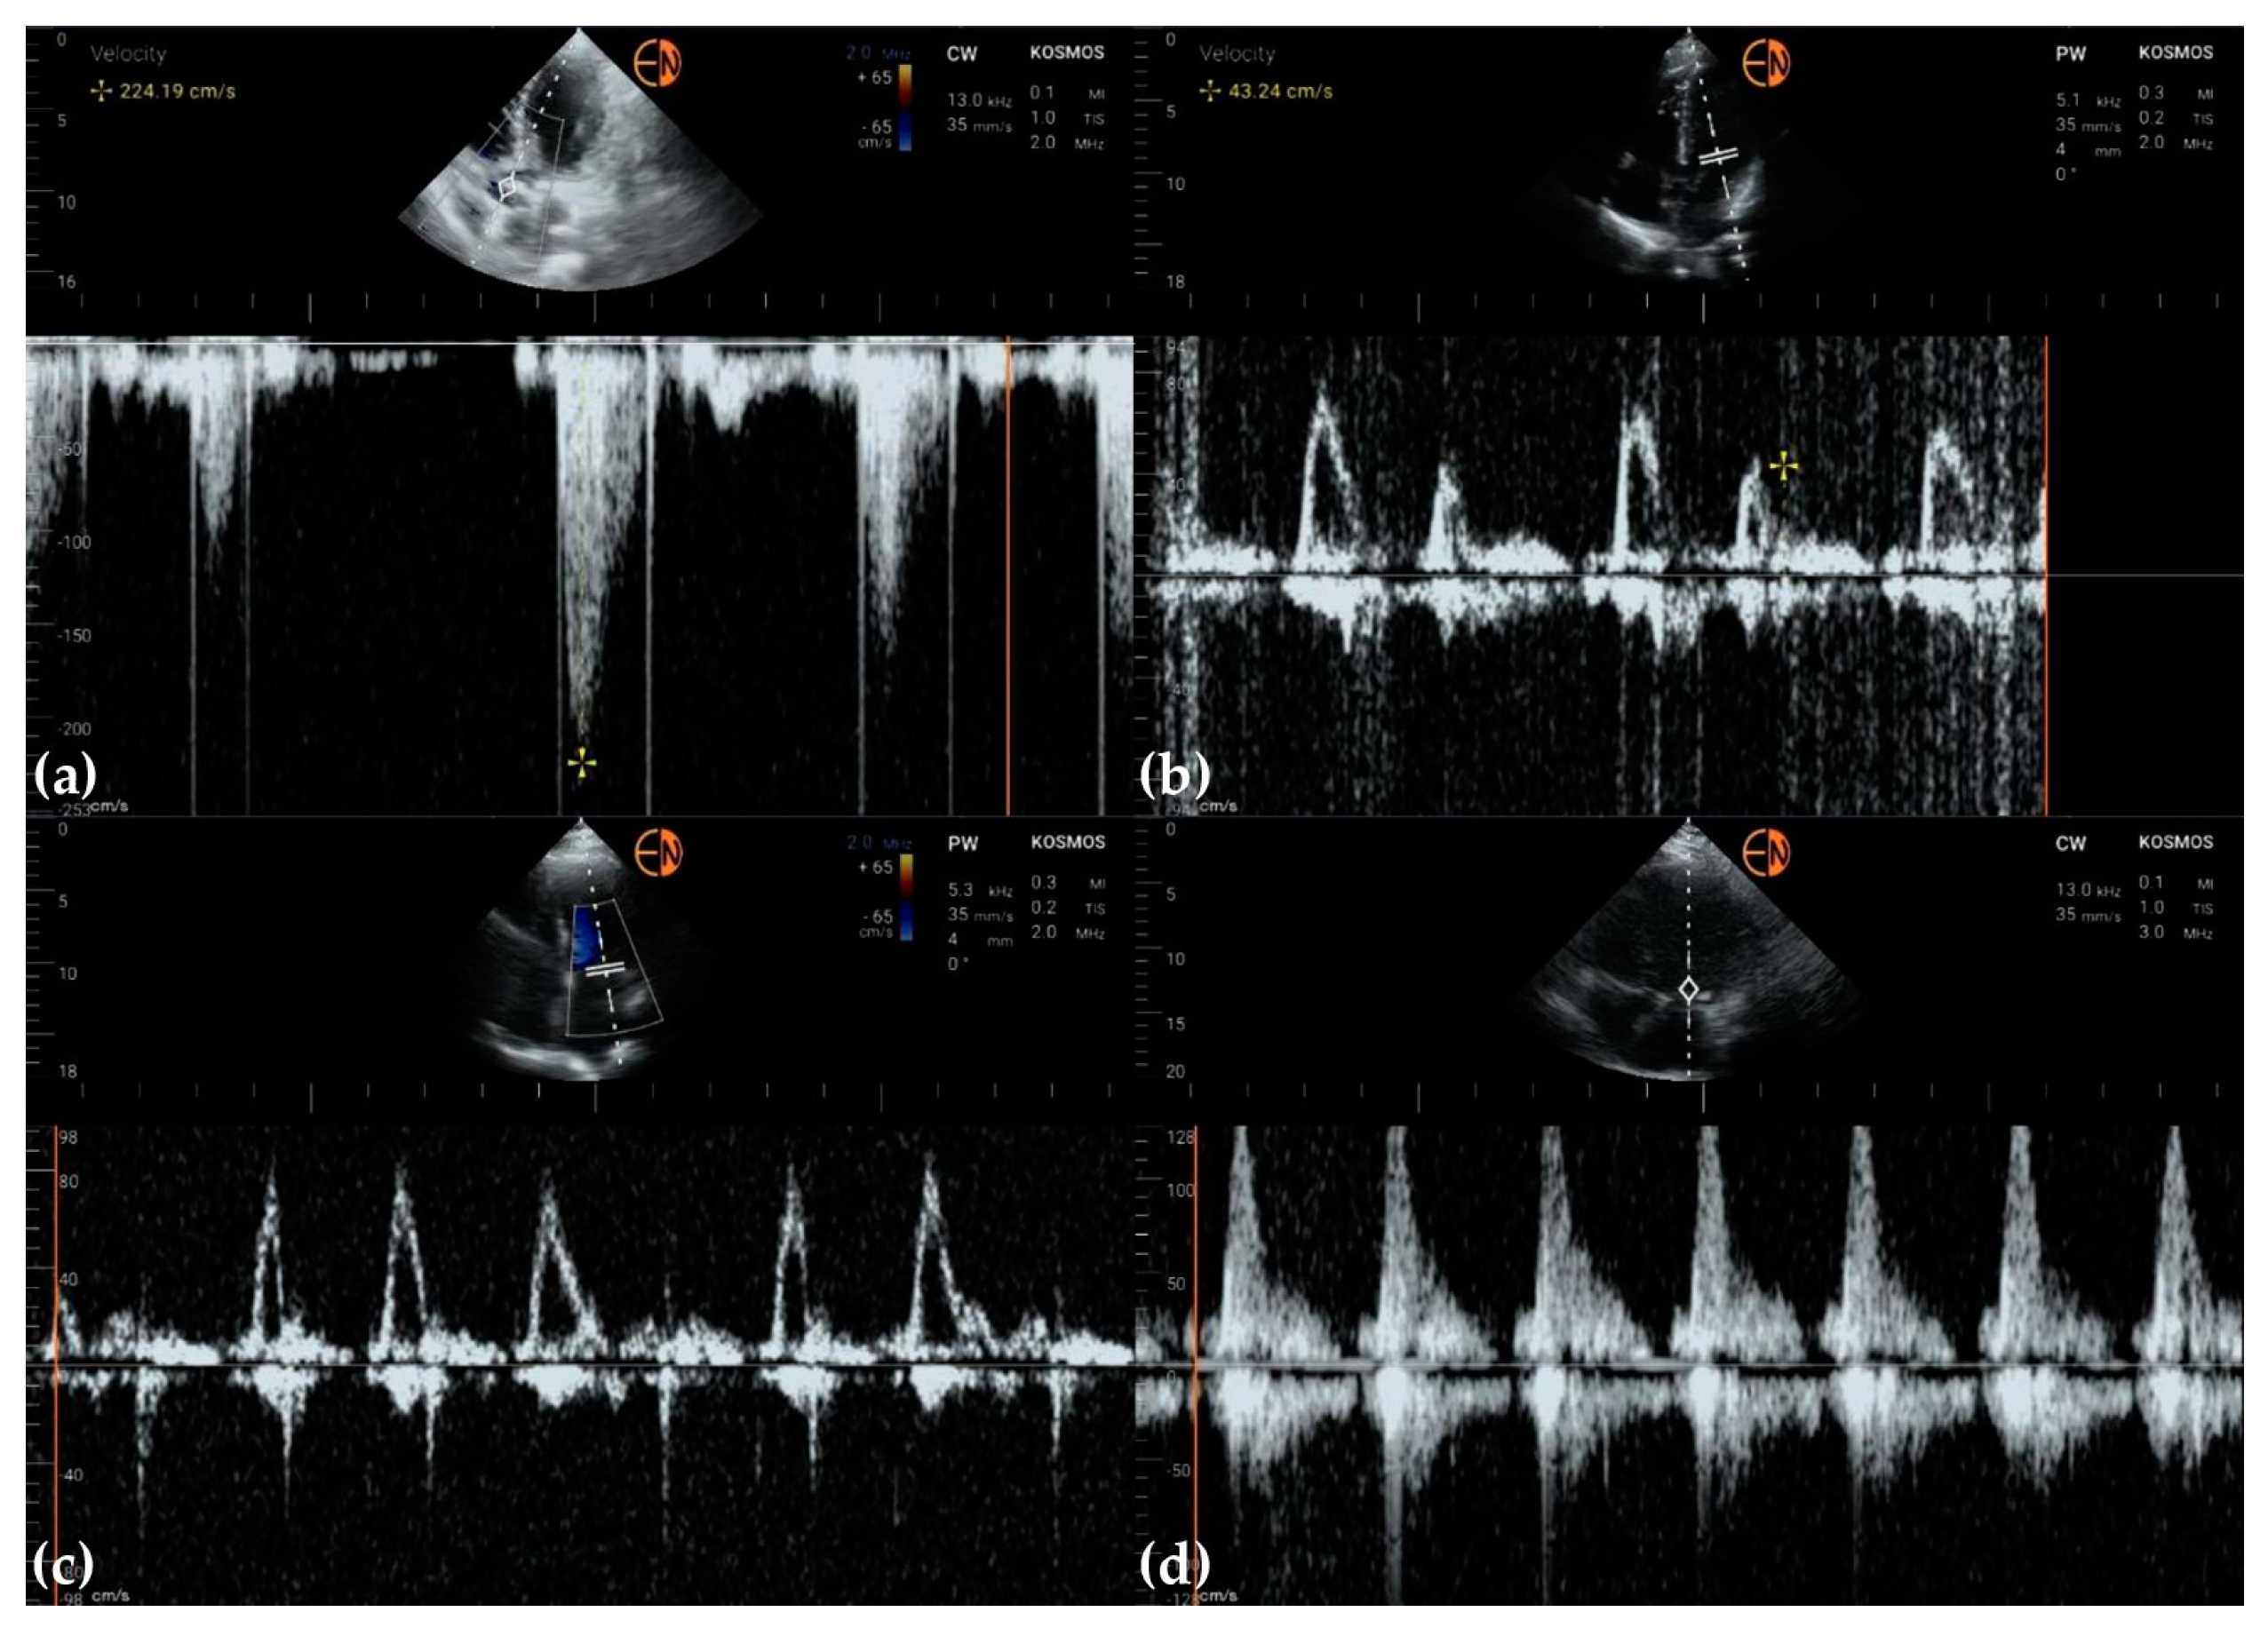

3.3. Valvular Stenosis and Regurgitation

3.4. Other Findings